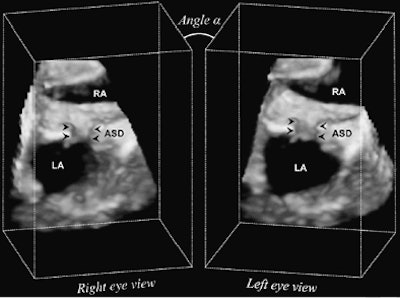

| The volumetric dataset of the created ASD (arrowheads) is sampled using parallel projection. Rays are cast simultaneously in a front-to-back fashion through the 3D ultrasound data. Left-eye and right-eye views are separately generated by rendering the 3D ultrasound volume from two viewpoints skewed by angle A. LA = left atrium; RA = right atrium. Image published with permission of the Journal of Thoracic and Cardiovascular Surgery. |